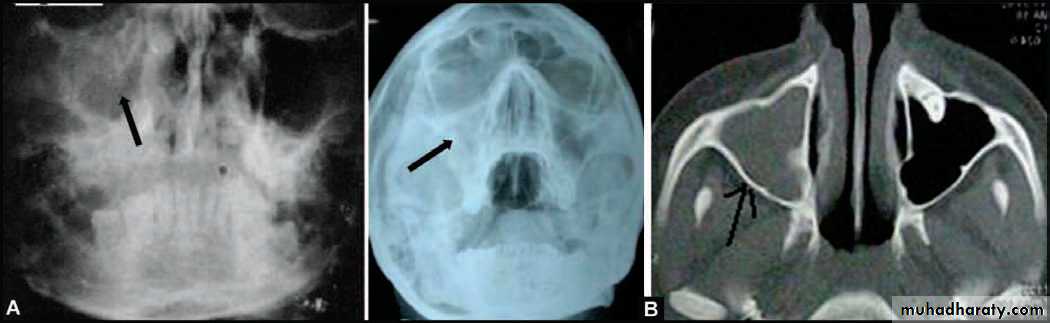

• Occipitomental View (15° OM): it’s called Water’s view. The presence of pus will produce a horizontal fluid level in this view; provided that there is air above it. As a measure of confirmation of the diagnosis, the view is repeated with the head tilted toward the side of pathology. The fluid level remains horizontal.

RadiographyRadiographic signs of sinus pathology :

Air fluid levels

Partial or complete opacification

Bony wall displacement

4 mm or more of mucosal wall thickening

Water’s view with air-fluid level in left maxillary sinus

Water’s view showing air-fluid level in right maxillary sinus and mucosal thickening in left maxillary sinus

(A) PA view of Water’s position showing haziness of the (R) maxillary sinus, following extraction of upper right first molar 3 months back. Chronic maxillary sinusitis with oroantral fistula (B) PA view Water’s position and CT scan picture of another patient showing complete haziness of (R) maxillary sinus, indicating chronic maxillary sinusitis